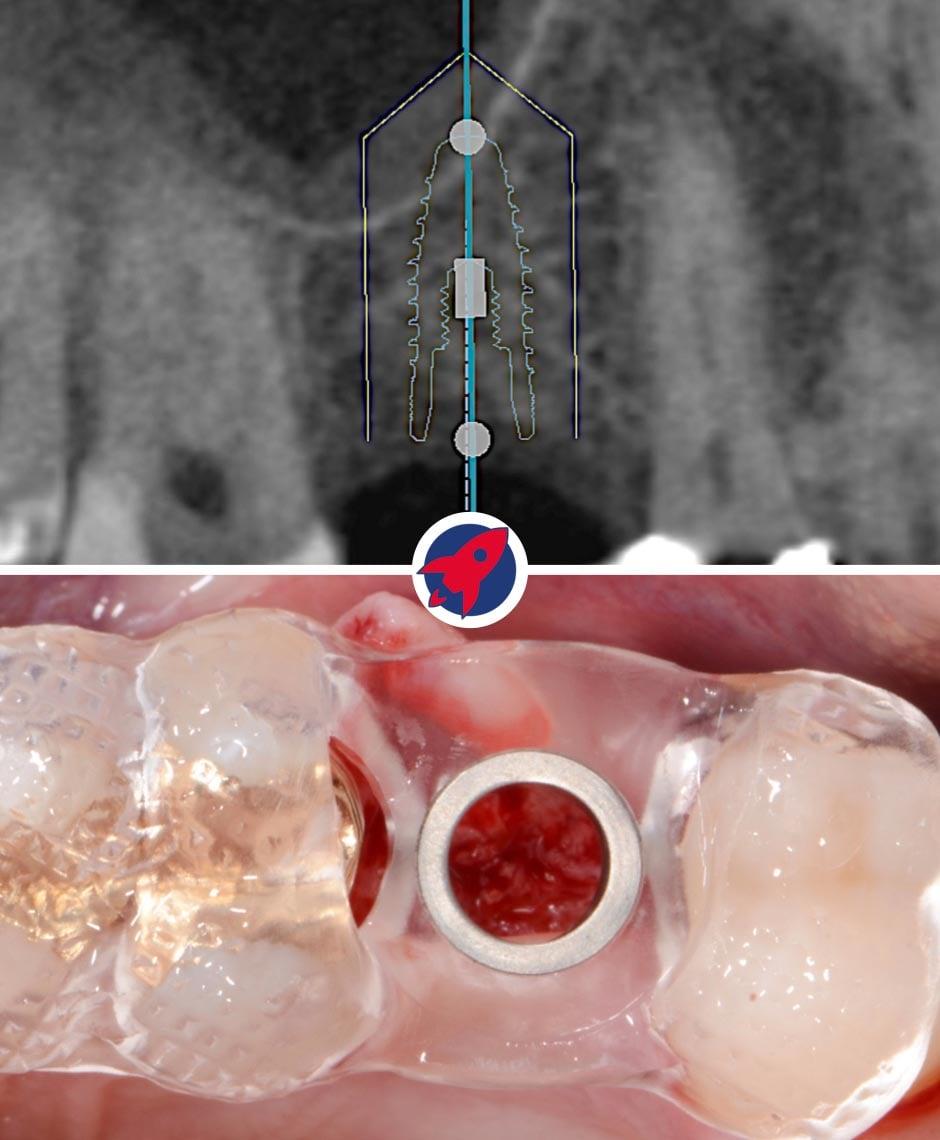

Digitale Planung & Schablonenfertigung

Basierend auf den DVT-Daten (Bild oben) erstellen wir die exakte Position, Länge und Neigung des Implantats am Computer. Bei Bedarf fertigen wir eine hochpräzise Bohrschablone an (unten).

Planung eines Zahnimplantats mittels 3D-Bildgebung: Ein detailliertes 3D-Röntgenbild zeigt die exakte Positionierung eines Zahnimplantats im Kiefer. Die Grafik illustriert die präzise Implantatplanung mit sichtbaren Messlinien für eine passgenaue Einbringung zwischen den Zähnen.